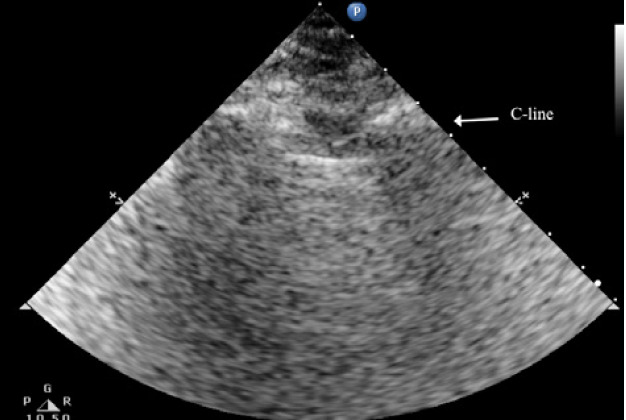

The C lines are defined as hypoechoic sub-pleural focal images produced by condensed lung tissue without the presence of the visceral pleural line gap. They are typically conical or dome-shaped, thus the name cupola (Figure 2b). C lines are not true lines but are designated as such in order to maintain consistency.22

Typical patterns of ultrasound imaging are seen at various scanning points during the diagnosis of pneumonia. From the anterior perspective, typical C-lines identified by a curvilinear aspect of the pleural line are caused by adjacent consolidated tissue; as in pneumonia, the alveoli are filled with fluid (Figure 3). The non-aerated lung tissue is thus readily transverse by ultrasound beams, producing an image comparable with liver tissue.7,18